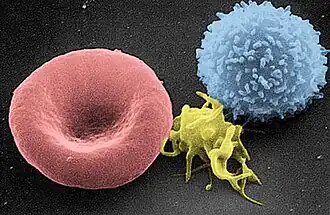

Blood is composed of blood cells suspended in blood plasma. Plasma, which constitutes 55% of blood fluid, is mostly water (92% by volume),[2] and contains proteins, glucose, mineral ions, and hormones. The blood cells are mainly red blood cells (erythrocytes), white blood cells (leukocytes), and (in mammals) platelets (thrombocytes).[3] The most abundant cells are red blood cells.[4] These contain hemoglobin, which facilitates oxygen transport by reversibly binding to it, increasing its solubility.[5] Jawed vertebrates have an adaptive immune system, based largely on white blood cells. White blood cells help to resist infections and parasites. Platelets are important in the clotting of blood.

Blood accounts for 7% of the human body weight,[9][10] with an average density around 1060 kg/m3, very close to pure water's density of 1000 kg/m3.[11] The average adult has a blood volume of roughly 5 litres (11 US pt) or 1.3 gallons,[10] which is composed of plasma and formed elements. The formed elements are the two types of blood cell or corpuscle – the red blood cells, (erythrocytes) and white blood cells (leukocytes) – and the cell fragments called platelets[12] that are involved in clotting. By volume, the red blood cells constitute about 45% of whole blood, the plasma about 54.3%, and white cells about 0.7%.

- 4.7 to 6.1 million (male), 4.2 to 5.4 million (female) erythrocytes:[13] Red blood cells contain the blood's hemoglobin and distribute oxygen. Mature red blood cells lack a nucleus and organelles in mammals. The red blood cells (together with endothelial vessel cells and other cells) are also marked by glycoproteins that define the different blood types. The proportion of blood occupied by red blood cells is referred to as the hematocrit, and is normally about 45%. The combined surface area of all red blood cells of the human body would be roughly 2,000 times as great as the body's exterior surface.[14]

- 4,000–11,000 leukocytes:[15] White blood cells are part of the body's immune system; they destroy and remove old or aberrant cells and cellular debris, as well as attack infectious agents (pathogens) and foreign substances. The cancer of leukocytes is called leukemia.

- 200,000–500,000 thrombocytes:[15] Also called platelets, they take part in blood clotting (coagulation). Fibrin from the coagulation cascade creates a mesh over the platelet plug.